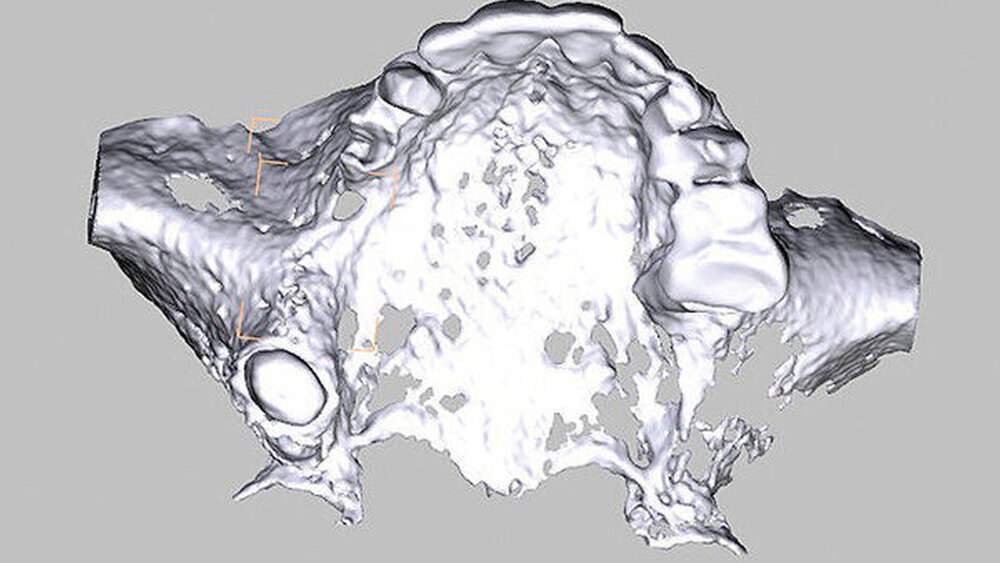

Aufgrund einer ausgeprägten Alveolarkammatrophie im Bereich des rechten Oberkiefers wurde uns eine 62-jährige Patientin zur Augmentation und Implantation überwiesen. Sie hatte ein Implantat regio 16 aufgrund einer Periimplantitis verloren, der Zahn 14 war kurze Zeit vorher extrahiert worden, der Kieferkamm regio 15 war schon lange Jahre zahnlos. Nach wie vor kam für die Patientin nur festsitzender Zahnersatz infrage. Zahn 18 war zwar noch in situ, für eine Brückenversorgung war die Schaltlückenspanne von Zahn 13 auf Zahn 18 aber deutlich zu groß. Nach eingehender klinischer und radiologischer Untersuchung, ausführlicher Besprechung aller Alternativen und einer eingehenden Risikoaufklärung entschied sich die Patientin für die Alveolarkammrekonstruktion mittels CAD/CAM-gefertigtem individualisierten allogenen Knochenblocks. Die DICOM-Daten des angefertigten Oberkiefer-DVTs wurden an die botiss biomaterials GmbH übermittelt. Dort wurde der allogene Spenderblock digital designt, virtuell wurden Implantate aufgestellt und die Planung wurde zur Korrektur zurück an unsere Praxis gesendet. Nach Freigabe durch den Operateur konnte mit der Fertigung des allogenen Blocks begonnen werden.

Die Schnittführung wurde nach dem Pillar-Sockel-Design (Blume) vorgenommen. Dabei liegt die Inzision weit im Vestibulum und verbindet zwei vertikale Entlastungsschnitte. Im Gegensatz zu der herkömmlichen krestalen Schnittführung bleibt das Periost über dem augmentierten Bereich damit völlig intakt. Nach der streng subperiostalen Präparation erfolgte die Kontrolle der Passung des CAD/CAM-Blocks. Ein ganz entscheidender Punkt ist, vor jeglichem Kontakt des Blockes mit Blut diesen in steriler Kochsalzlösung und am besten in der PRF-Flüssigkeit zu wässern, sodass sich keine Poren des Blocks mit Blutkoageln verschließen und innerhalb des Blocks ein nicht mit Blut gefüllter Hohlraum bildet. Vor der Befestigung des Blocks wurde die Kompakta des Empfängerbetts mit einer kleinen Kugelfräse mehrfach perforiert um sogenannte Bleeding Points zu setzen, die die Durchblutung des Knochenblocks gewährleisten. Mit zwei Osteosyntheseschrauben mit dem Durchmesser 1,5 mm und der Länge 9 mm wurde der allogene Knochenblock rotationssicher fixiert. Das Augmentat wurde mit einer dünnen Schweinepericard-Membran (Jason membrane, botiss biomaterials GmbH, Vertrieb Straumann) und der PRF-Membran abgedeckt. Der spannungsfreie Wundverschluss erfolgte mit der modifizierten vertikalen Matratzennaht nach Laurrell mit resorbierbarem Nahtmaterial (Vicryl 4.0). Postoperativ wurde ein Oberkiefer-DVT angefertigt. Die Nahtentfernung wurde im Rahmen der Nachsorgeuntersuchung sieben und 14 Tage postoperativ vorgenommen. Nach einer Heilzeit von sechs Monaten erfolgte die Implantation in Lokalanästhesie unter antibiotischer Abschirmung mit 2 g Amoxicillin oral eine Stunde präoperativ. Die Schnittführung erfolgte krestal, und nach subperiostaler Präparation wurde der Knochenblock dargestellt und die Osteosyntheseschrauben wurden entfernt. Danach wurden drei Implantate (Straumann) in den Knochenblock gesetzt und mit 0er-Verschlussschrauben abgedeckt. Die Wundrandadaptation erfolgte mit resorbierbarem Nahtmaterial, das bei der Verlaufskontrolle sieben Tage postoperativ vollständig entfernt wurde. Nach dreimonatiger gedeckter Einheilung wurden die Implantate im Rahmen einer Vestibulumplastik freigelegt. Dafür wurde eine erneute krestale Schnittführung regio 14 bis 17 vorgenommen und ein Splitflap präpariert. Der vestibuläre Wundrand wurde mit Einzelknopfnähten im Vestibulum fixiert. Im Bereich der Implantate wurde der Splitflap perforiert, um die Abdeckschrauben gegen Gingivaformer auszutauschen, und der Bereich des nun freiliegenden Bindegewebes wurde mit einer 3D-vernetzten Kollagenmatrix (mucoderm, botiss biomaterials GmbH, Vertrieb Straumann) abgedeckt. Diese wurde zunächst gewässert, um die Verarbeitung zu erleichtern, und an den Stellen der Gingivaformer gestanzt. Die Nahtentfernung erfolgte neun Tage postoperativ. (Abb. 1a bis 1f).